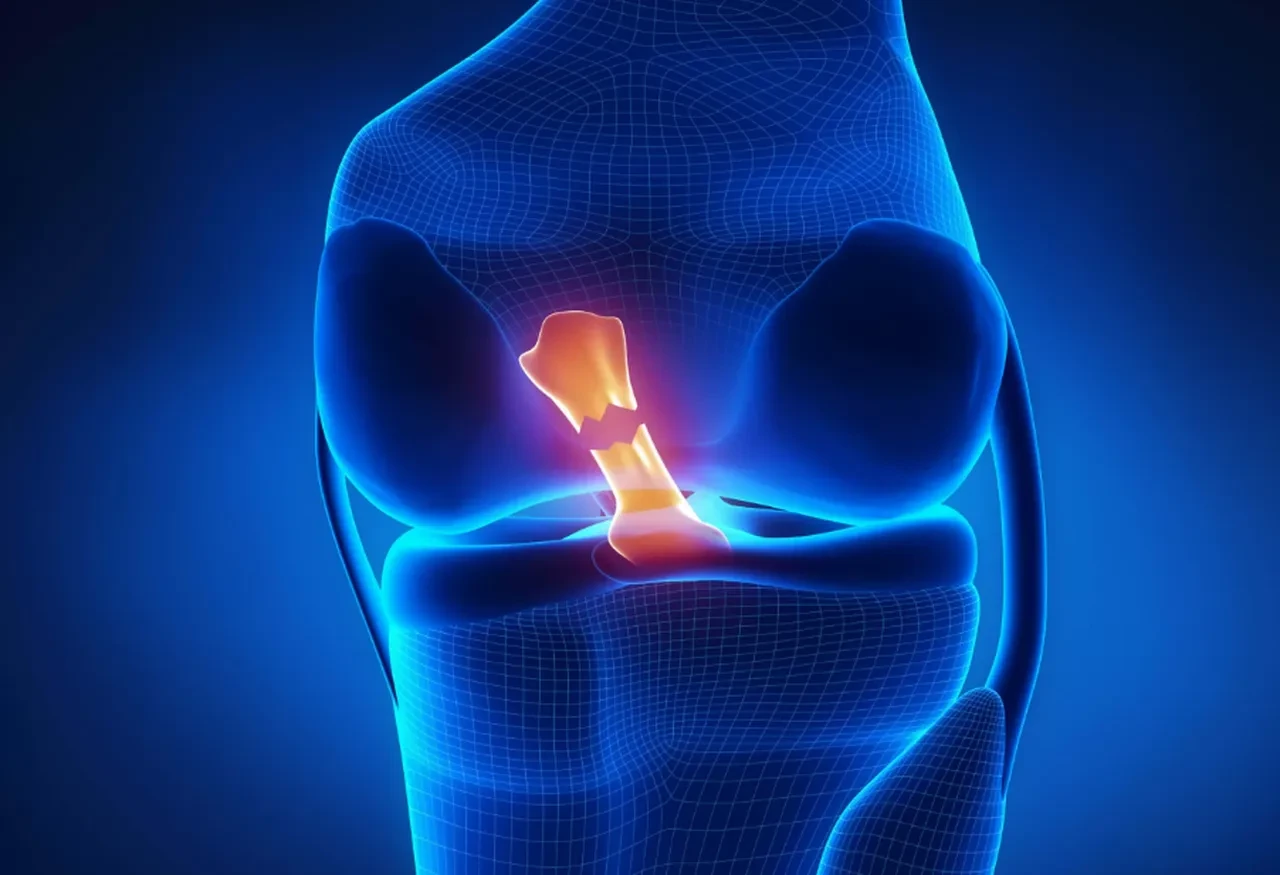

Bilim insanları dizlerdeki bu sesin kesin nedenini hâlâ tam olarak bilmiyor. Olası açıklamalar arasında eklem kıkırdaklarının yıpranması, tendonların kemik üzerinde hareket etmesi veya eklem sıvısındaki küçük gaz kabarcıklarının patlaması bulunuyor. Yani bu durum çoğu zaman normal bir süreç olabilir.

Gençlerde de dizlerden ses gelmesi olağan bir durum. Özellikle diz yaralanması veya cerrahi müdahale sonrası bu ses daha sık görülüyor. Araştırmalara göre, böyle bir durumda kısa vadede kıkırdak hasarı riski artsa da, uzun vadede bu durum daha kötü bir iyileşme ya da ciddi eklem hastalıkları anlamına gelmiyor.